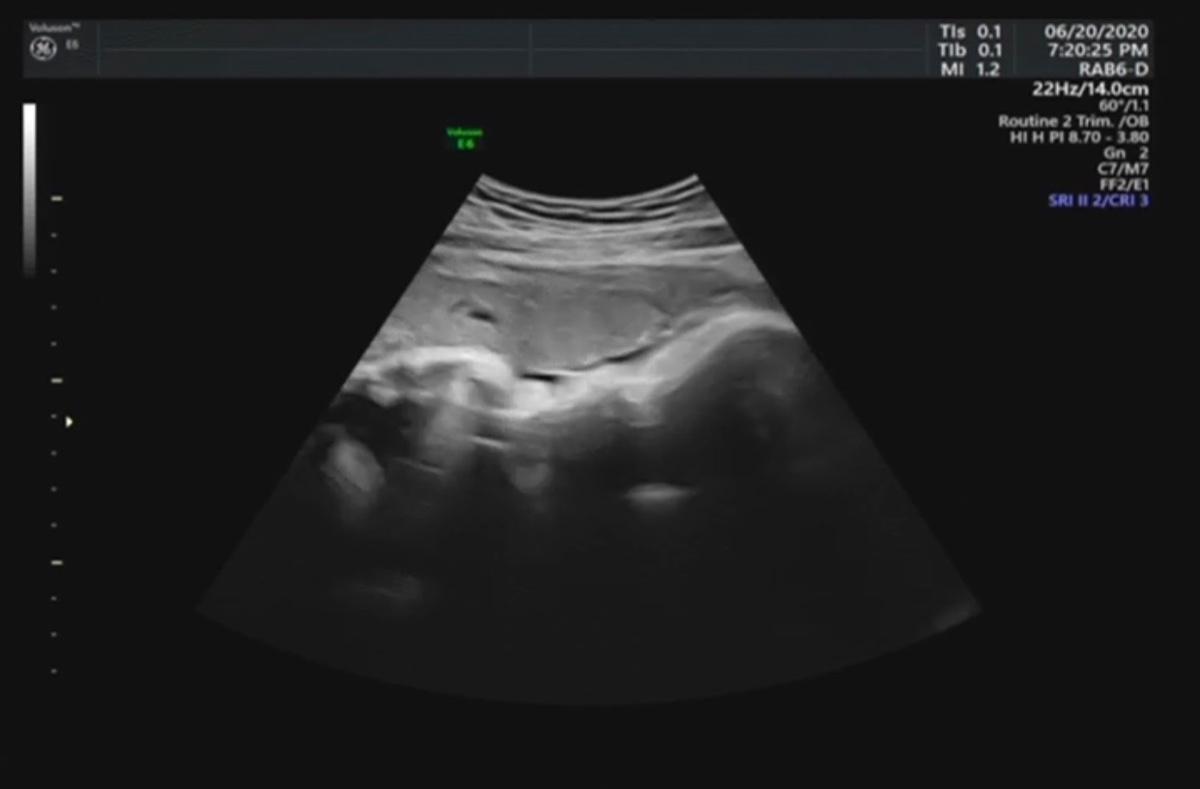

週六去產檢,照超音波的時候,醫生發現,我的羊水突然驟降,從原本的8降為2,醫生說這樣有點危險,因此立馬建議我們星期一來醫院催生~